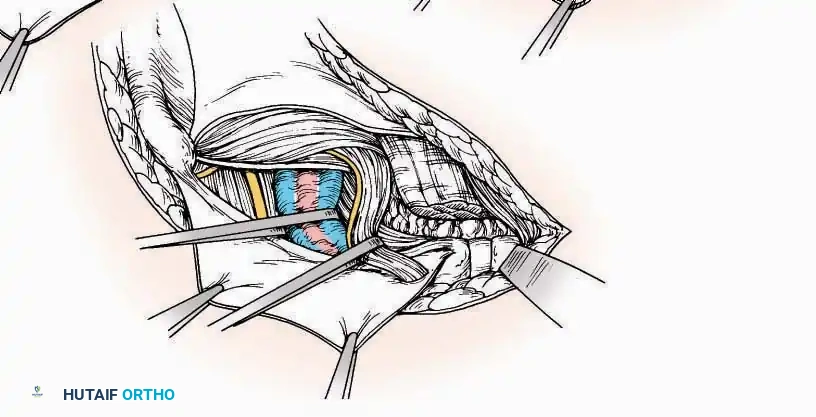

Lateral Approach (Extensile Lateral)

This is the workhorse approach for open reduction and internal fixation (ORIF) of displaced intra-articular calcaneal fractures.

Indications: ORIF of calcaneus fractures, lateral wall exostectomy, subtalar arthrodesis.

Positioning: Lateral decubitus with the operative leg up, or supine with a large bump under the ipsilateral hip to internally rotate the leg.

Surgical Technique:

* Incision: Begin the incision on the lateral margin of the Achilles tendon near its insertion. Extend it distally to a point 4 cm inferior and 2.5 cm anterior to the lateral malleolus. (For trauma, a classic L-shaped extensile incision is often used, dropping straight down anterior to the Achilles, then curving gently toward the base of the 5th metatarsal).

* Superficial Dissection: Divide the superficial and deep fasciae. It is imperative to create a "full-thickness" flap containing skin, subcutaneous fat, and periosteum to prevent flap necrosis.

* Nerve Protection: The sural nerve crosses the proximal and distal limbs of this approach. It must be identified and protected within the anterior flap.

* Deep Dissection: Isolate the peroneal tendons (longus and brevis). Incise and elevate the periosteum below the tendons to expose the lateral wall of the calcaneus.

* Tendon Management: If severe deformity or infection is present, the peroneal tendons may be divided via Z-plasty and repaired at the conclusion of the case, though this is rarely necessary in modern fracture care.